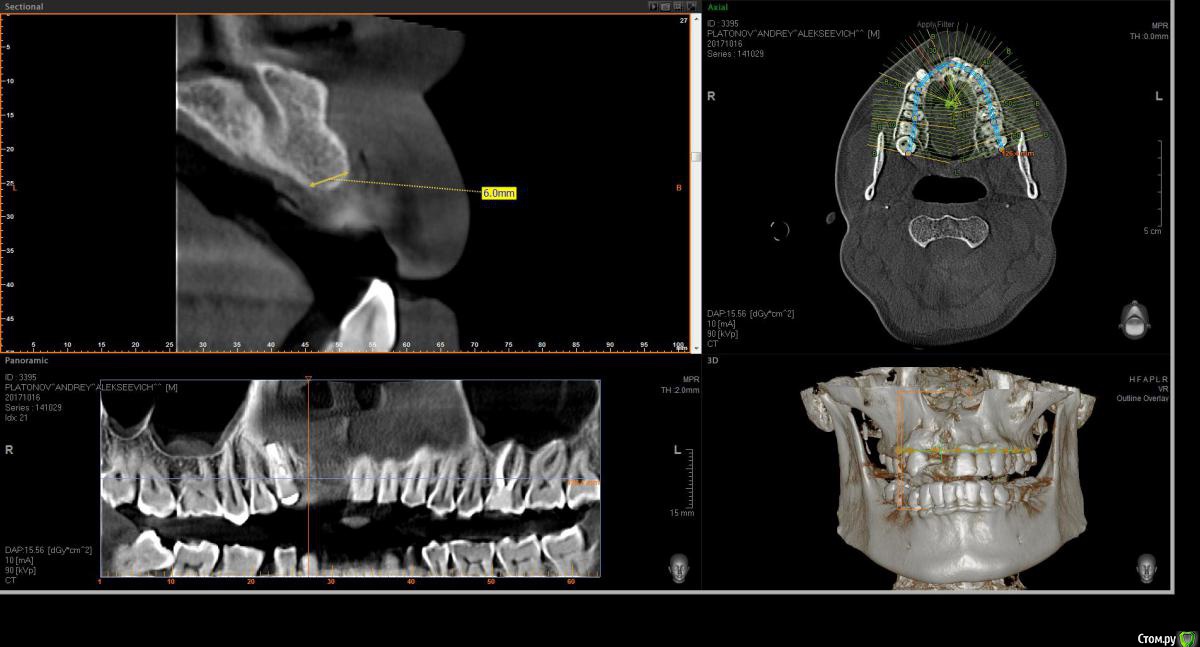

Eddie Опубликовано 23 октября, 2017 Поделиться Опубликовано 23 октября, 2017 (изменено) Здравствуйте! Подскажите по планированию имплантации. 11- удален 4-5 месяцев назад, 12-несколько лет назад. Пациент на данный момент носит съемник.как лучше позиционировать имплантаты? возможно ли обойтись без нкр, а поработать конденсорами? Еще смущает, что в области 11 возможно дефицит кости после удаления? Если ставить 11 чуть ближе к 21, то там условия по-лучше, но до 21 расстояние 1.5 мм или даже чуть меньше!В клинике только Ankylos. Реально ли будет отпротезировать при таких позициях?Буду благодарен любым советам. P.S. пациент финансово не потянет нкр Изменено 23 октября, 2017 пользователем Eddie Ссылка на комментарий

Bier Опубликовано 25 октября, 2017 Поделиться Опубликовано 25 октября, 2017 не вижу уровня гребня. Фотки бы. По тому что я вижу, имплантат в область 12 с Анкилос как раз подойдет. + десна в область 12 и 11.Если это ваш первый кейс, боюсь, что вы его запорите. Ссылка на комментарий

Eddie Опубликовано 25 октября, 2017 Автор Поделиться Опубликовано 25 октября, 2017 (изменено) не вижу уровня гребня. Фотки бы. По тому что я вижу, имплантат в область 12 с Анкилос как раз подойдет. + десна в область 12 и 11.Если это ваш первый кейс, боюсь, что вы его запорите.Спасибо за ответ. В клинике я один хирург! Отказаться вряд ли получится. Есть опыт установки имплантатов в области жевательных зубов, опыт работы с десной. Если всё-таки буду ставить, в области 12 в плане вестибуло-орального положения и наклона как лучше спозиционировать? Изменено 25 октября, 2017 пользователем Eddie Ссылка на комментарий

Bier Опубликовано 25 октября, 2017 Поделиться Опубликовано 25 октября, 2017 Нет, пациент готов еще без зуба походитьнаклон не имеет принципиального значения. Я бы ставил четко по гребню. Вестибуло-орально центр имплантата должен смотреть в слепую ямку предполагаемого зуба. Для этого начинать сверление нужно на 0,5-1мм нёбнее с давлением на нёбную стенку, чтобы имплантат в итоге не встал вестибулярно. Я бы откинул лоскут в области 12 и туннелировал офтальмологическим скальпелем область 11. Понадобятся внутрибороздковые разрезы в области 21з взять ССТ и завести его правую часть под слизистую в области 11з, а левую надеть на формик. Формирование овоида не ранее, чем через 6 недель после операции. Ссылка на комментарий